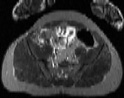

Visible Human male: Sectio transversalis 1794

CT

NMR

Pd                          / T2 \                         T1